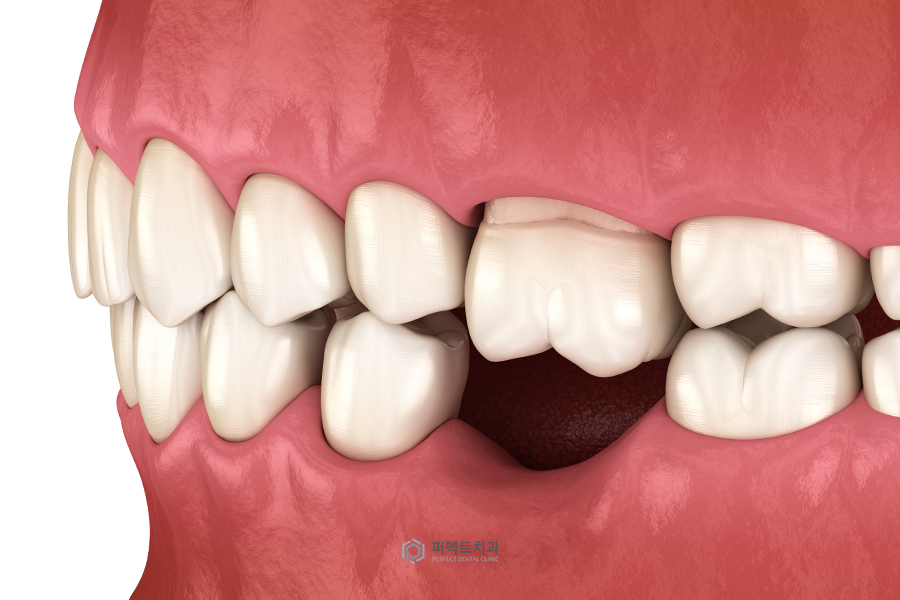

또 다른 케이스는 어금니가 없는 경우 임플란트 치료를 받는 분들이 많은데, 어금니가 빠진지 오랜 시간이 지난 경우에는 반대쪽 대합치가 과도하게 내려와서 임플란트를 심고 싶어도 식립 할 공간이 부족한 경우가 있습니다.

이 때 반대쪽에 미니스크류를 식립하면 최소한의 치아에 장치를 부착하고도 정출(치아가 정상범위보다 맹출됨)된 치아를 원래의 위치로 조절 할 수 있습니다.